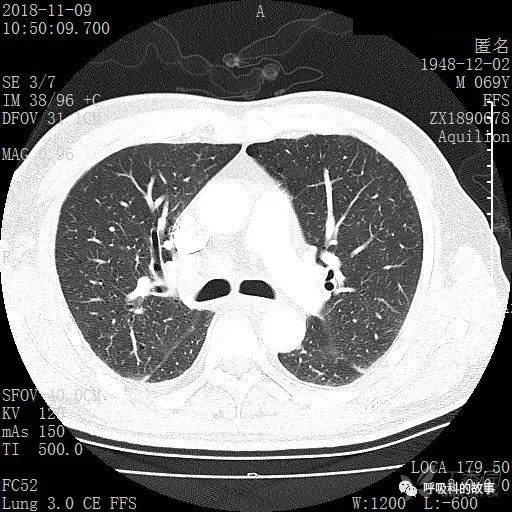

胸部增强CT示右肺门占位伴远端阻塞性肺炎,纵膈、右肺门、右侧颈根部、右侧腋下及肝门部肿大淋巴结。两侧胸腔少量积液。

肺窗CT